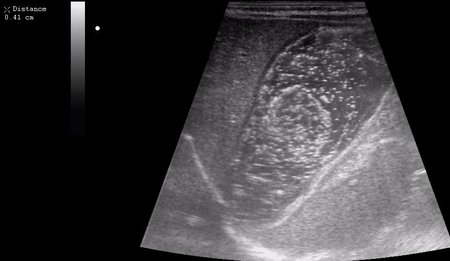

Ребёнок 1 месяц 10 дней от родy, с отсуствием прибавки в весе.

Hypertrophic pyloric stenosis.

Criteria:

1.Pyloric channel > 12 mm in length

2.Muscular layer thickness > 3-4 mm

3.Donuts sign at transverse scanning

Dr.Mario писал(а): 3.Donuts sign at transverse scanning

Признак "пончика".

А что, похоже.